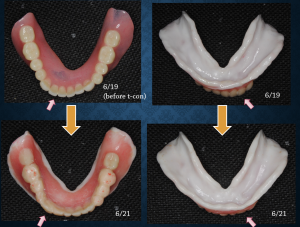

残っている歯が数本あって、それらを抜いて総入れ歯にする場合には治療用義歯に粘膜調整材という白い軟性の材料を使って理想的な形を追求していくことが多いです。この作業は結構奥が深くて、術者の経験やイメージに左右されます。どういう形がその患者さんにとって最も口の中で安定し快適なのか。無から有を作り出す総義歯医療はやりがいもある反面、困難なケースにも対応できるように常に勉強、準備が必要と思います。勉強と言っても本や単発の講習会参加だけでは私の場合には十分でないように思います。以前から参加し続けている咬合セミナー、勉強会のメンバーは1日中総義歯だけでお互いのケースを提示しながら活発な討論ができるので非常に助かっています。総義歯医療については、たとえ患者さんが満足したとしても、もっとこうすればよかったのではないか、もっとうまくなりたい、などという思いは尽きることがありません。

理想的な形を追求(東京大手町勤務歯科医の総義歯、全顎治療ブログ)